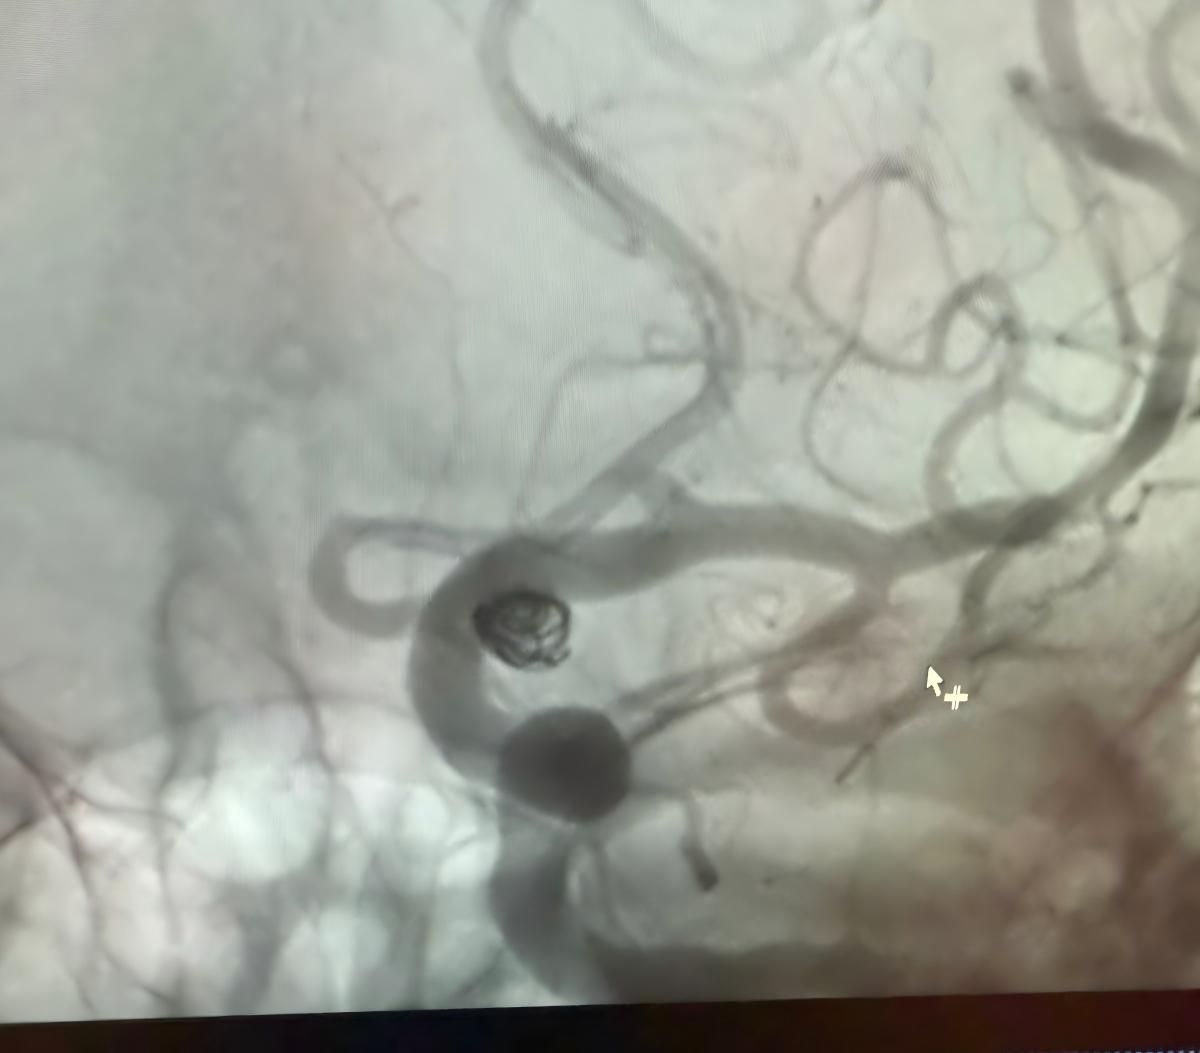

The treatment utilized the Nuva® Flow Diverter (TJED-D 5.0–14), Perdenser® 3D coil, and Frepass® Microcatheter (TJMC18 Plus) for a posterior communicating artery aneurysm.

Dr. Mutis highlighted the excellent visibility of the device and noted that retrieving was smooth. He expressed great satisfaction with the final outcome.